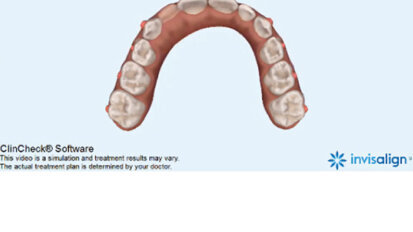

Bělení zubů a ortodoncie

St. 9. září 2020